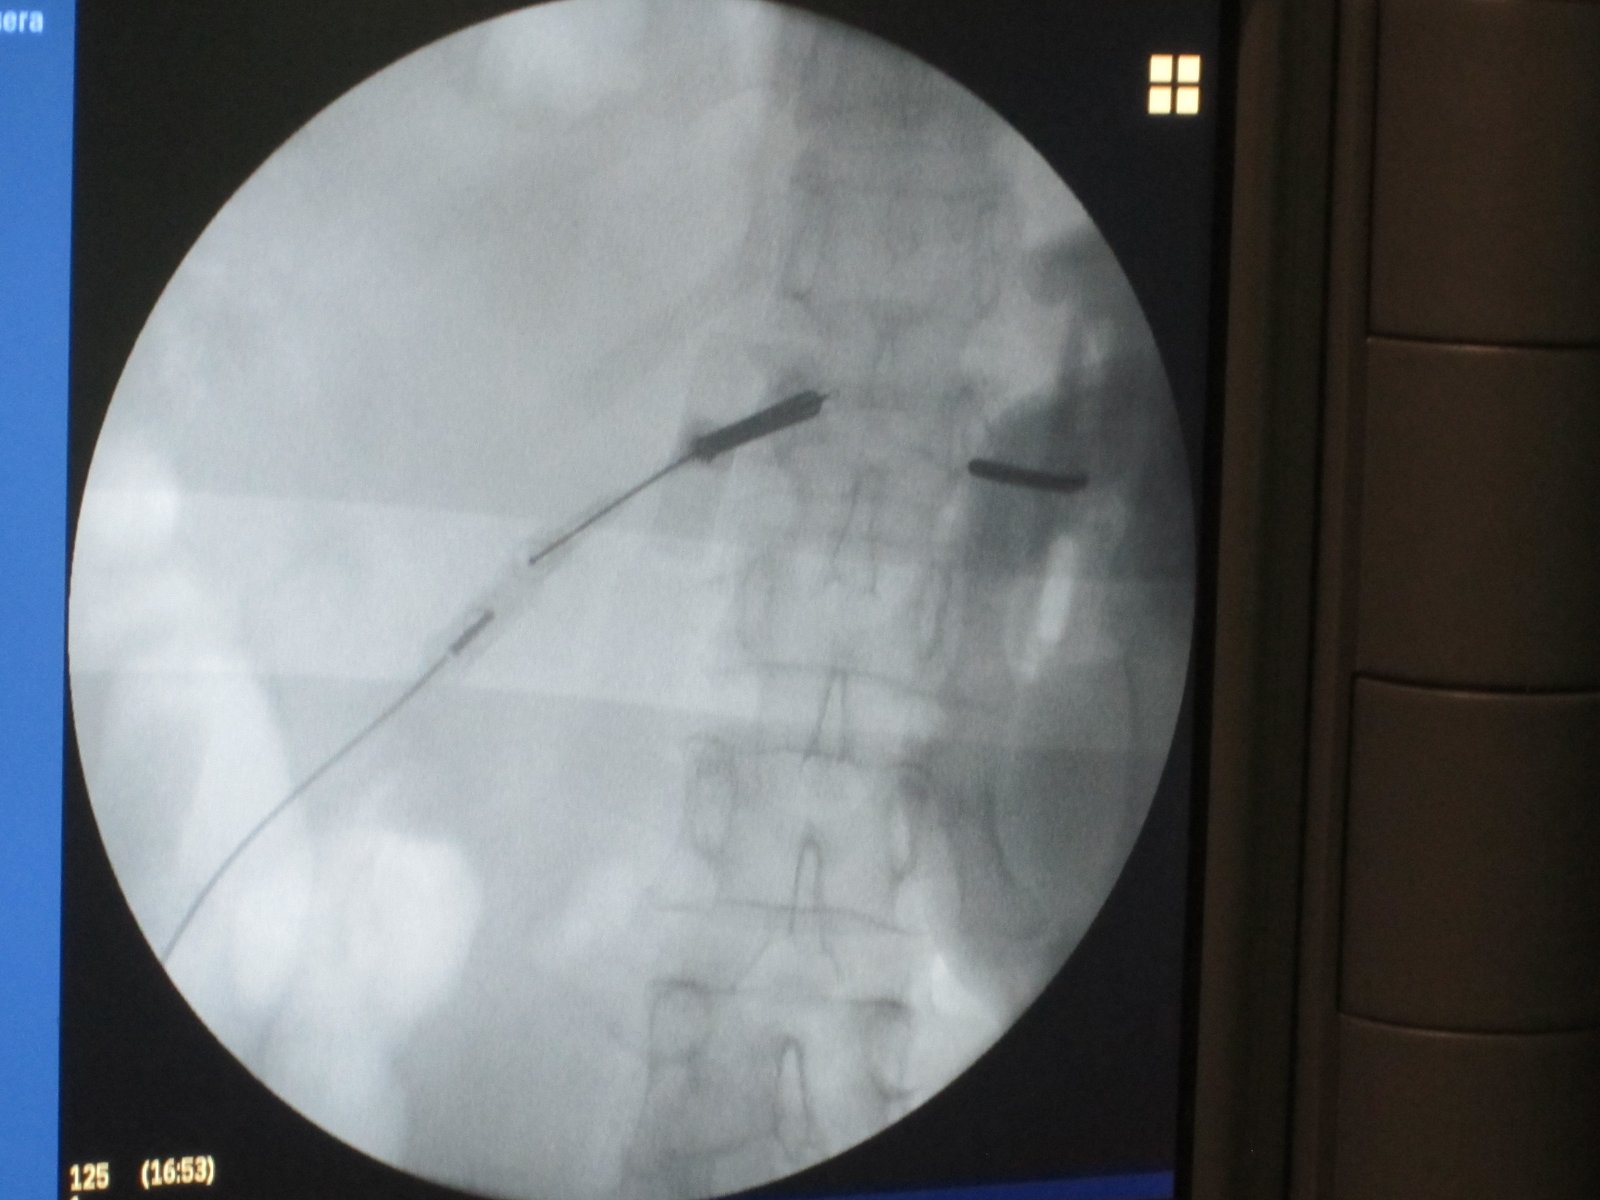

Estimulador de Cordones (SCS)

Tecnología que calma el dolor de forma automática, sin necesidad de cirugía mayor.